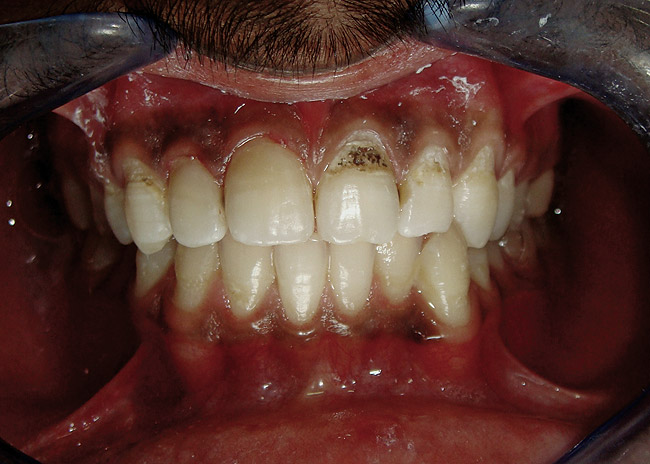

Figure 2  Caries extending cervically on upper right incisors.

Figure 2

Figure 3  Placement of rubber dam with application of cervical clamp on central incisor for extra retraction.

Figure 3

Figure 4  Final composite restorations with respect to upper right incisors.

Figure 4